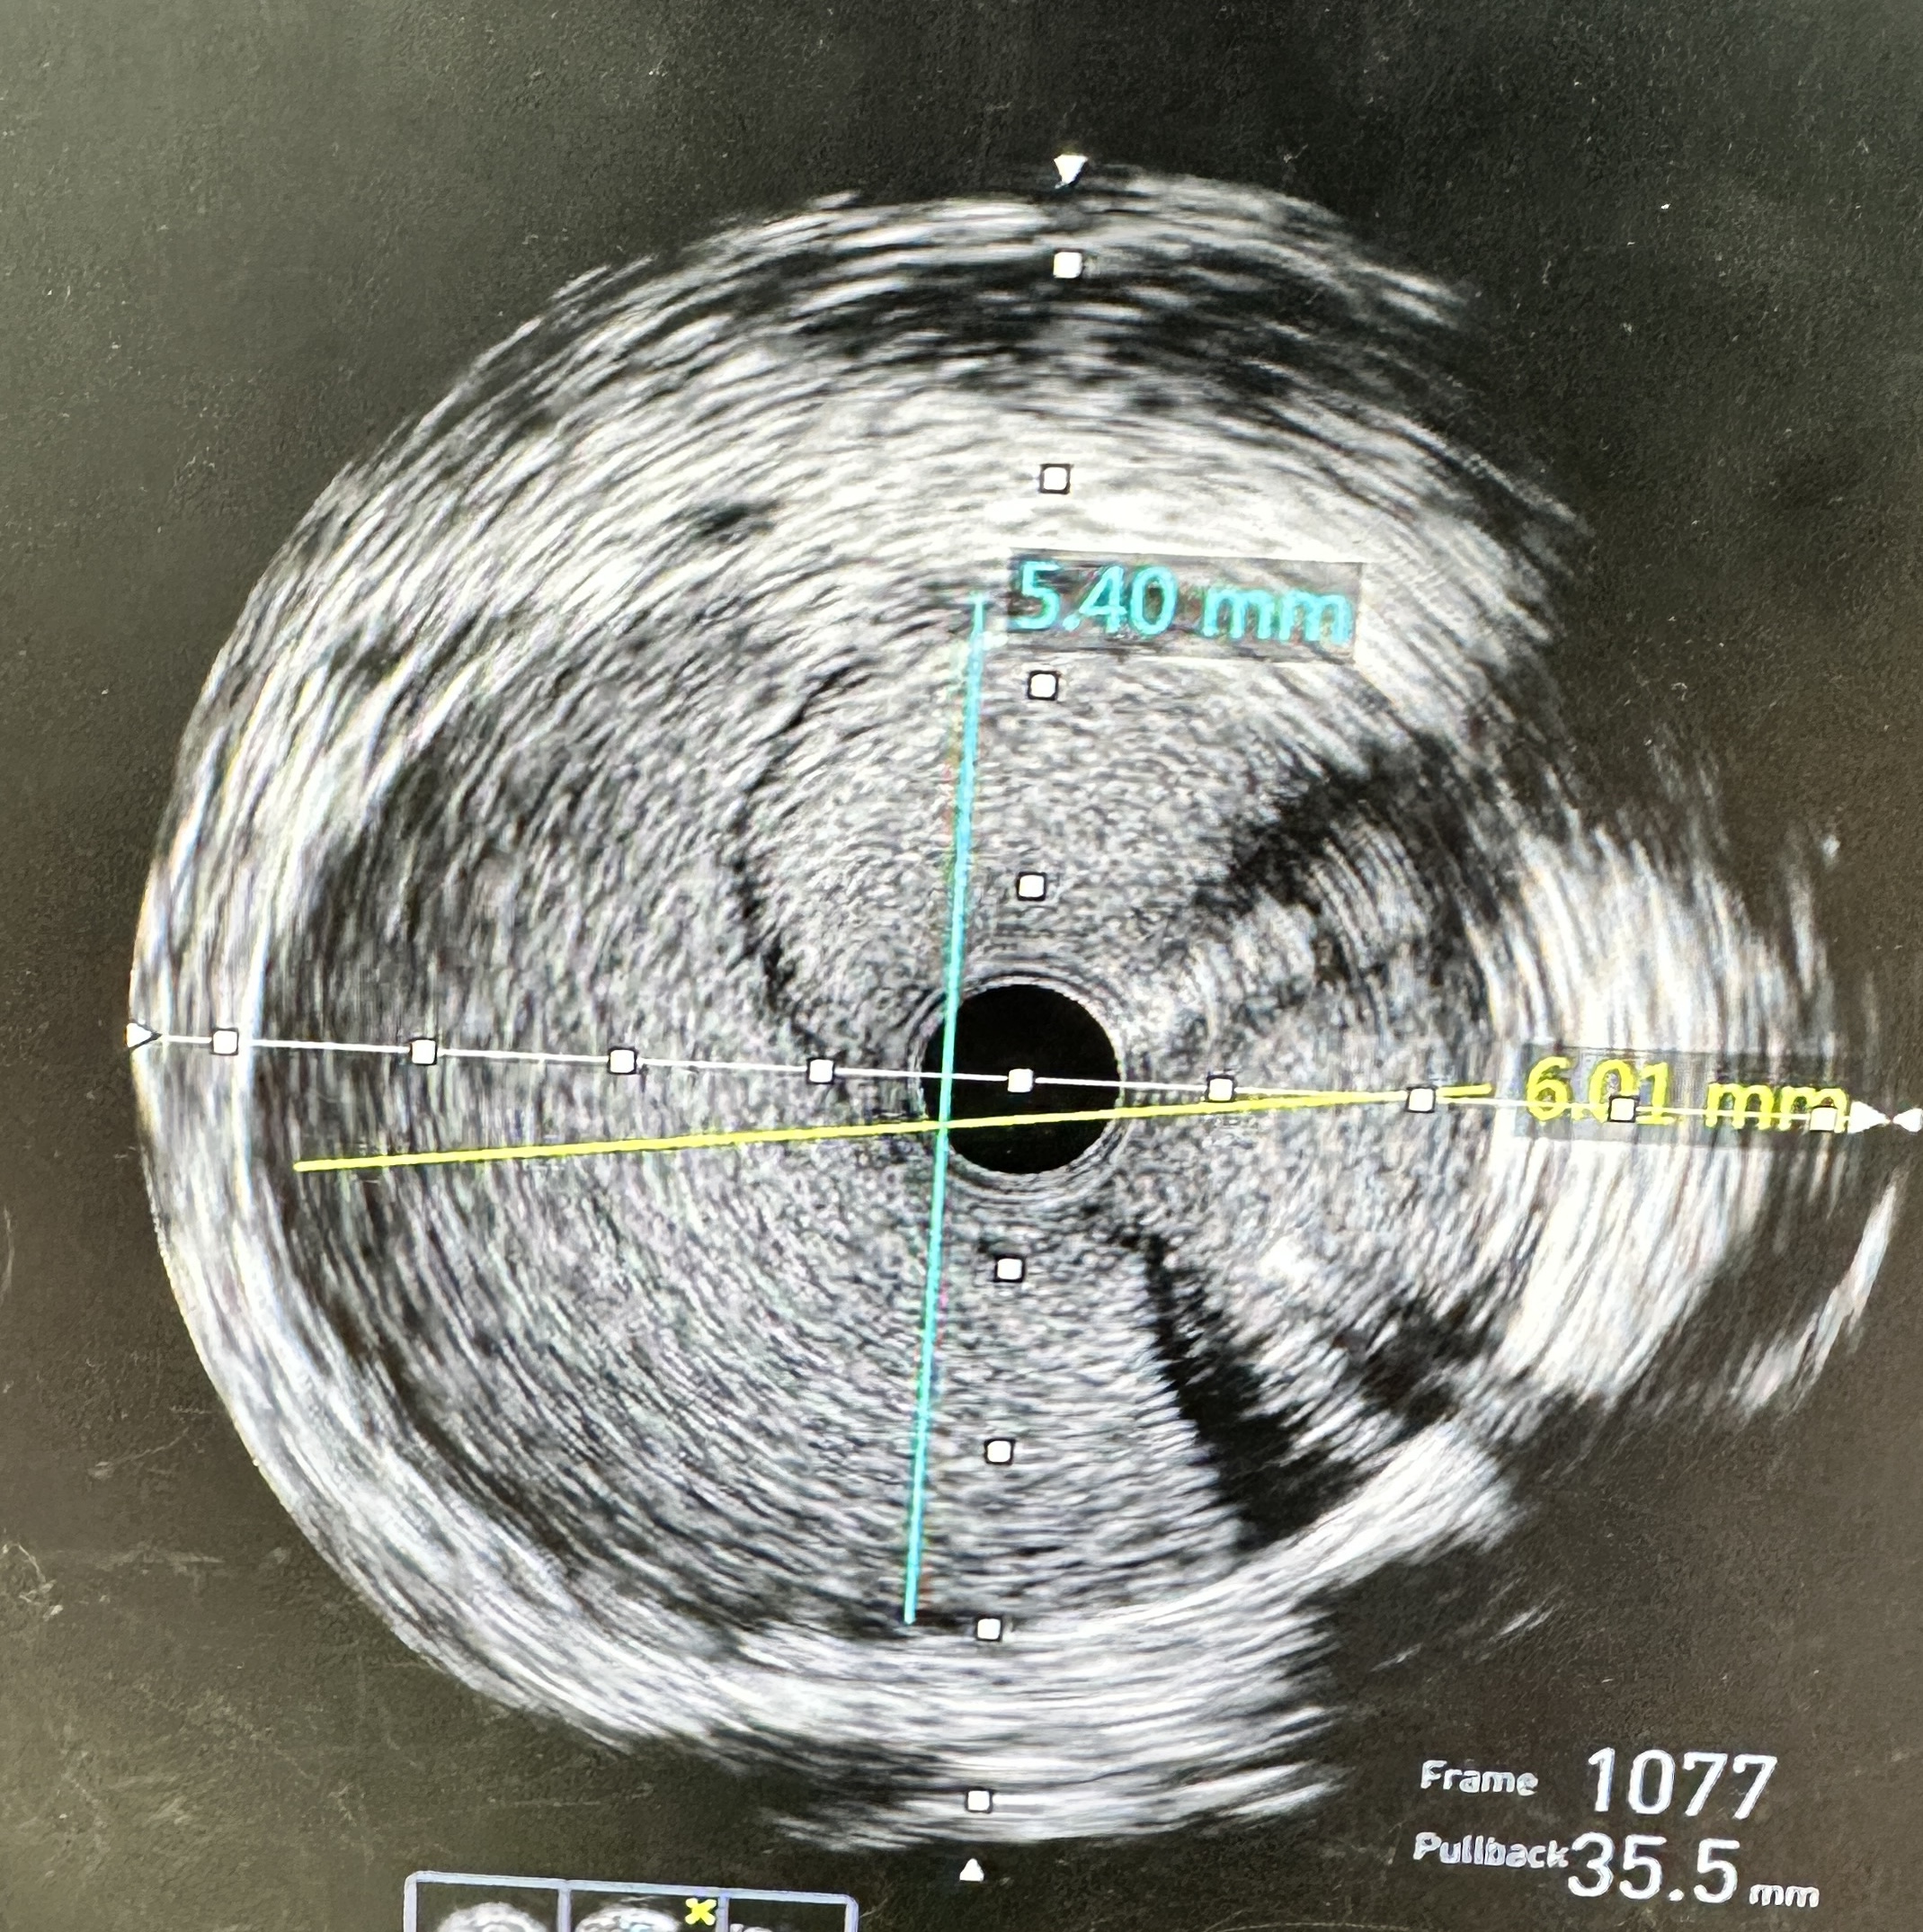

- Actions: Stopped contrast injections; converted to RFA for stronger guide backup. Wired LAD and LCX in true lumen (confirmed by IVUS).

- Imaging: IVUS pre-PCI confirmed dissection/intimal flap with intramural hematoma extending into proximal LAD/LCX; post-PCI showed good expansion/apposition, no residual entry.